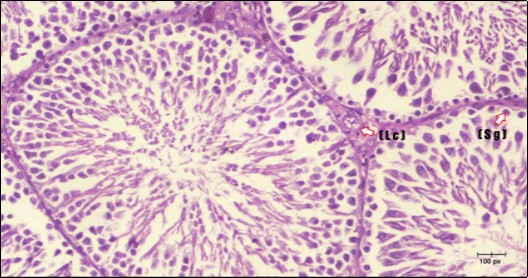

Figure 5.Photomicrogragh of testis section of treated rat with Fenugreek showing noticeable improvement with increased number of spermatogenic cells included moderate amount of spermatozoa (star) and organized Sertoli cells (arrow). Note liquid infiltration (dashed arrow) in wide interstitial tissue (H&E) (40x).

Photomicrogragh of testis section of treated rat with Fenugreek showing noticeable improvement with increased number of spermatogenic cells included moderate amount of spermatozoa (star) and organized Sertoli cells (arrow). Note liquid infiltration (dashed arrow) in wide interstitial tissue (H&E) (40x).

Figure 6.Photomicrogragh of testis section of treated rat showing increased number of spermatogenic cells from spermatogonia till spermatozoa (star). Few liquid infiltration in wide interstitial tissue (H&E) (40X).

Photomicrogragh of testis section of treated rat showing increased number of  spermatogenic cells from spermatogonia till spermatozoa (star). Few liquid infiltration in wide interstitial tissue (H&E) (40X).